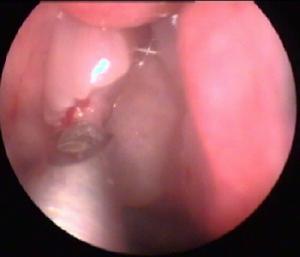

前鼻鏡檢查常可見灰白色的光滑莖蒂向後伸展。若用麻黃素棉片充分收縮鼻甲,還可看到莖蒂起自中鼻道,觸查質軟並可移動。後鼻鏡檢查可見息肉半透明,呈淡紅色或灰白色,位於後鼻孔或鼻咽部。墜入咽部的息肉在軟齶上舉時更易看清。